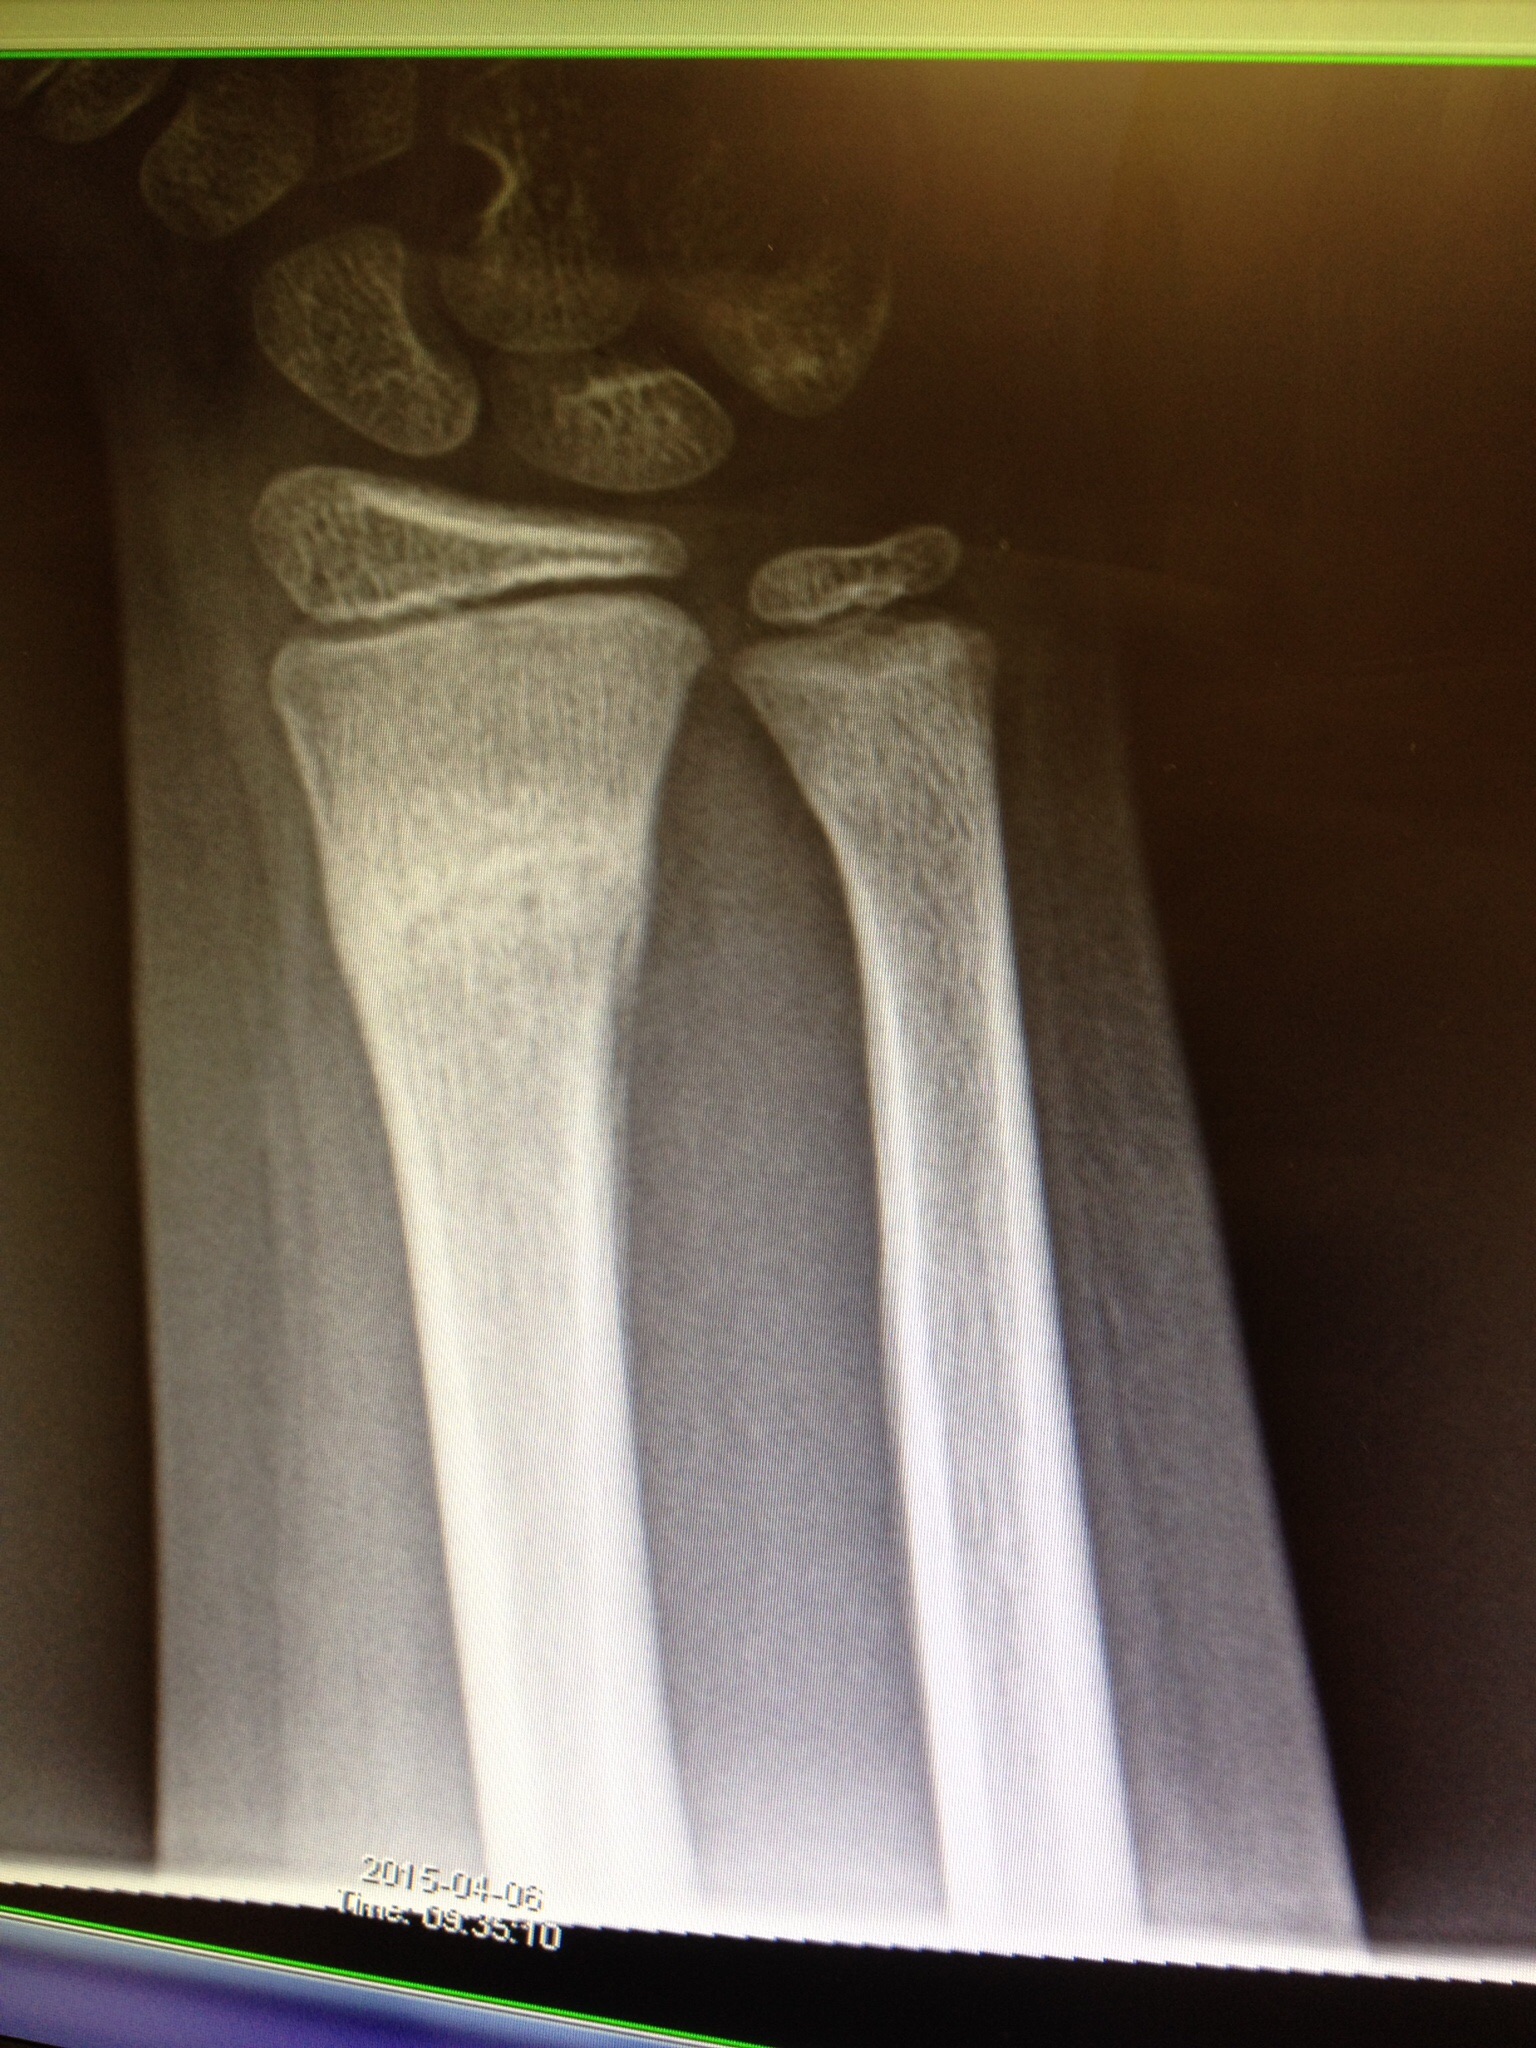

Gissa om hon blev glad när sjukskötaren kom in med den speciella lilla sågen som skulle avlägsna detta hårda gips, som ju egenligen inte är gips längre, utan gjort av glasfiber. Han sågade försiktigt upp på båda sidorna av gipset och tog sedan en tång och bröt upp det. Lillasyster såg på sin arm, som var styv och huden var en aning torr efter tre veckors vistelse under täcke, men märkvärdigare än så var det inte. Hon vände försiktigt på armen och det gick bra. Sjukskötaren tog med henne till röntgen för att ta en ny bild av armen hennes. Så här såg den ut:

Den vitare delen är det nya benbildningen och armen hennes har allså läkts väldigt fint och precis som väntat. Läkaren menade att inga extra åtgärder behövdes. Ta det lilla lugnet på rasten i skolan ännu den här veckan, men inkommande lördag får Lillasyster börja med gymanstik igen, precis som som hon gjorde innan fallet då hon bröt armen.